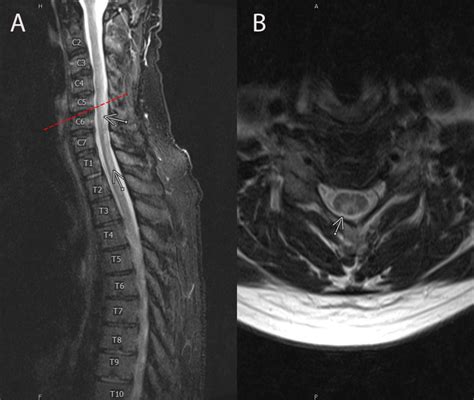

• Magnetic Resonance Imaging (MRI): To visualize the spinal cord and brain for signs of degeneration.

• subacute combined degeneration on mri